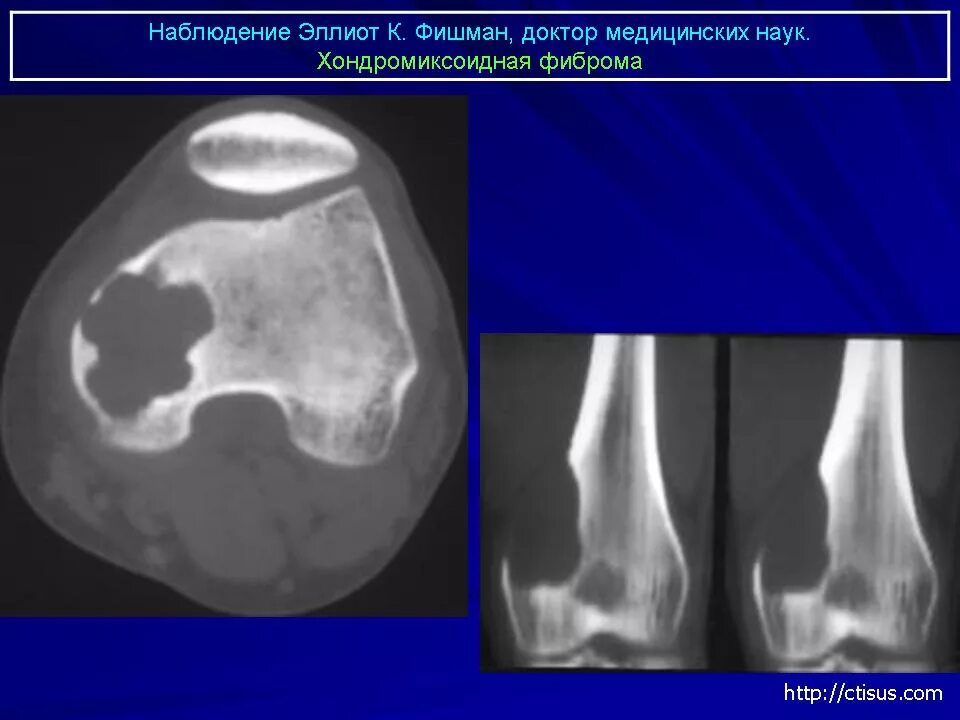

Фиброма кт